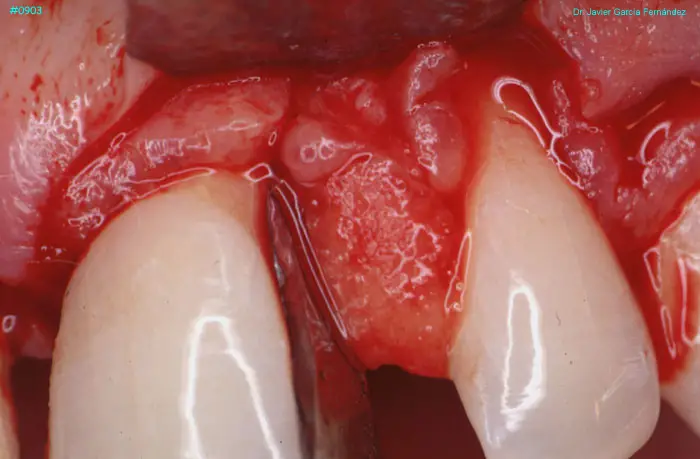

Atlas of Surgical Techniques in Periodontics. Chapter III. Atlas de Técnicas Quirúrgicas en Periodoncia